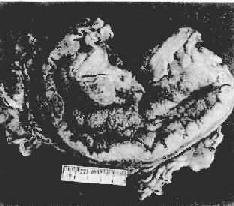

图10-16 弥漫浸润型胃癌

胃壁因癌组织的弥漫浸润而显著增厚